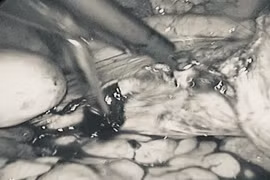

Phẫu thuật thành công lấy khối u xơ tử cung 30cm nặng 3,2 kg

Nhờ kỹ thuật phẫu tích tỉ mỉ, các bác sĩ đã bảo tồn được niệu quản, bàng quang cho bệnh nhân, đồng thời tiến hành thắt động mạch hạ vị phải để hạn chế chảy máu.